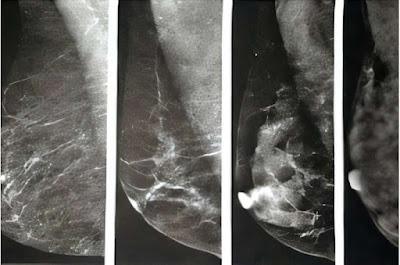

Las mamas contienen tres tipos principales de tejido: glandular, conectivo fibroso y graso. El tejido graso se ve oscuro en una mamografía, mientras que el tejido glandular y el conectivo fibroso se ven blancos. El problema es que los tumores también se ven blancos, lo que dificulta distinguir entre tejido mamario normal y cáncer.

Las mamas densas presentan mayor cantidad de tejido conectivo glandular y fibroso, y menor cantidad de tejido graso. La densidad mamaria se clasifica en cuatro categorías según el sistema BI-RADS del Colegio Americano de Radiología : Tejido mamario exclusivamente graso: Los senos están compuestos casi exclusivamente de tejido graso. Aproximadamente el 10 % de las mujeres presentan este tipo.

Tejido mamario fibroglandular disperso: Se presenta principalmente tejido graso con algunas zonas densas de tejido conectivo glandular y fibroso. Aproximadamente el 40 % de las mujeres presentan este tipo.

Tejido mamario heterogéneamente denso: Presenta numerosas áreas de tejido conectivo glandular y fibroso, con menos áreas de tejido graso. Aproximadamente el 40 % de las mujeres presentan este tipo.

Tejido mamario extremadamente denso: Tiene casi exclusivamente tejido conectivo glandular y fibroso. Aproximadamente el 10 % de las mujeres se encuentran en esta categoría y presentan un riesgo ligeramente mayor de cáncer de mama; se necesita más investigación para comprender por qué.

Se considera que las mujeres de los dos últimos grupos tienen "mamas densas".

Si su tejido mamario es exclusivamente graso o fibroglandular disperso, verá "no denso" en sus resultados. Si su tejido mamario es heterogéneo o extremadamente denso, verá "denso" en sus resultados.